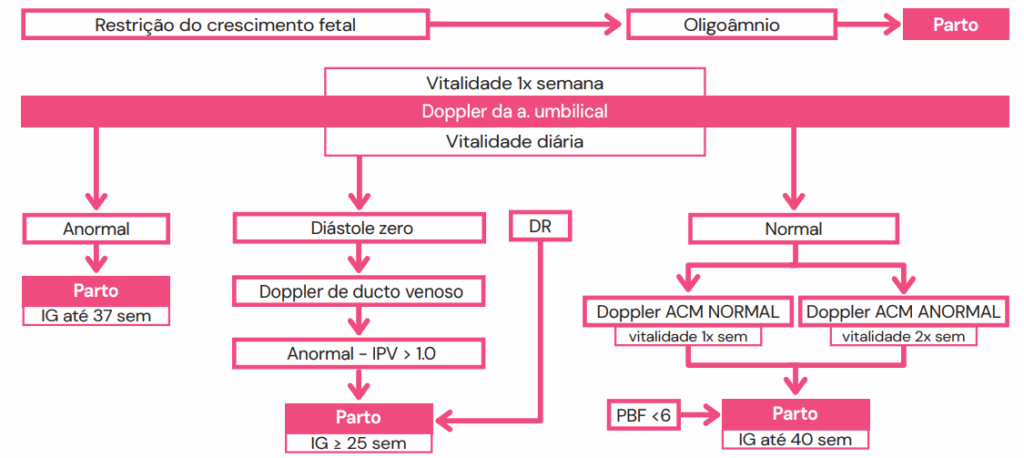

Conduta na RCF

O manejo da RCF é complexo e visa equilibrar o risco de prematuridade com o risco de óbito intraútero. A decisão sobre o momento do parto baseia-se na idade gestacional e na gravidade dos achados dopplerfluxométricos. De forma geral:

- Estágio 1 (alterações leves) ou PIG (Pequeno para a Idade Gestacional com Doppler normal): O parto pode ocorrer próximo ao termo (38-40 semanas).

- Estágio 3 (Diástole Zero na AU): O parto é recomendado por volta de 34 semanas, via cesárea.

- Estágio 4 (Diástole Reversa na AU): O parto é indicado a partir de 30 semanas, via cesárea.

- Estágio 5 (Onda ‘a’ reversa no DV ou CTG alterada): Indica-se o parto na viabilidade fetal, via cesárea.

Martinelli S, Zugaib M, Francisco RP, Bittar RE. Restrição do crescimento fetal. São Paulo: Federação Brasileira das Associações de Ginecologia e Obstetrícia (FEBRASGO); 2018. (Protocolo FEBRASGO – Obstetrícia, no. 35/ Comissão Nacional Especializada em Medicina Fetal).